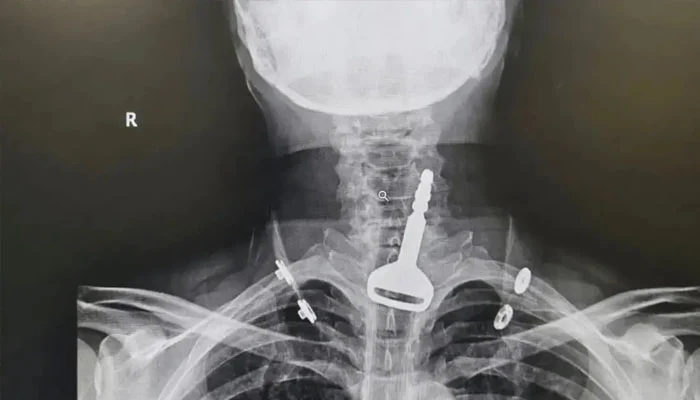

ڈاکٹروں پر مشتمل میڈیکل ٹیم نے ایکسرے سمیت متاثرہ شخص کے ضروری ٹیسٹ کروائے جس میں چابی پھنسے ہونےکی درست جگہ معلوم ہوئی۔

ڈاکٹروں نے متاثرہ شخص کا 15 منٹ میں آپریشن کرکے اس کی جان بچا لی جبکہ متاثرہ شخص دل کا بھی مریض تھا۔